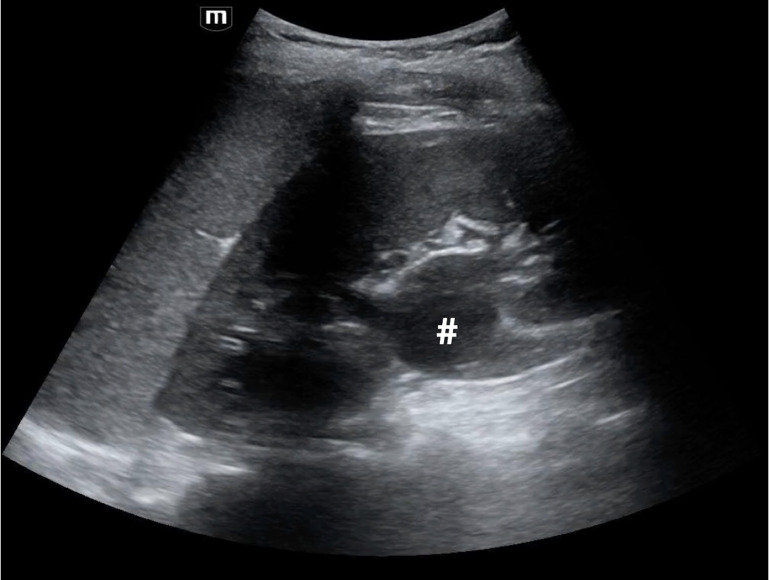

An 11-year-old postmenarchal female presented to the pediatric emergency department (ED) with 2 days of periumbilical and right lower abdominal pain. Radiology-performed ultrasound (RADUS) did not visualize the appendix, and there was a plan for surgical consultation to decide between serial abdominal exams versus computed tomography (CT) scan. While awaiting consultation and to help further narrow the differential diagnosis, the emergency provider performed a point of care ultrasound (POCUS) of the urinary tract. This revealed several anomalies including a solitary left kidney with hydronephrosis, and a well-circumscribed, fluid-filled structure with mixed echogenicity posterior to the bladder and inferior to the uterus. Given these findings on POCUS, further imaging was pursued, including a RADUS of the pelvis followed by a magnetic resonance imaging (MRI) of the abdomen. Further imaging ultimately diagnosed a bicornuate uterus, septate vagina with hematocolpos and solitary left kidney consistent with Obstructed Hemivagina and Ipsilateral Renal Anomaly (OHVIRA) syndrome. This case is an illustration of how POCUS is an invaluable tool to narrow the differential diagnosis and guide advanced imaging or consultation for both common and rare causes of pediatric abdominal pain.